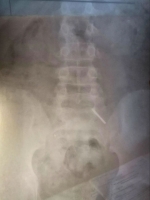

В клинику поступил 11-летний школьник, который, как оказалось, проглотил часть циркуля.

"Эндоскопически достать предмет не представлялось возможным из-за позднего обращения пациента. Главной задачей было не допустить перфорации кишечника и кровотечения - мальчик находился под наблюдением врачей и рентгенологов. В итоге инородное тело вышло естественным путем. Пациент выписан домой", - рассказали в больнице.